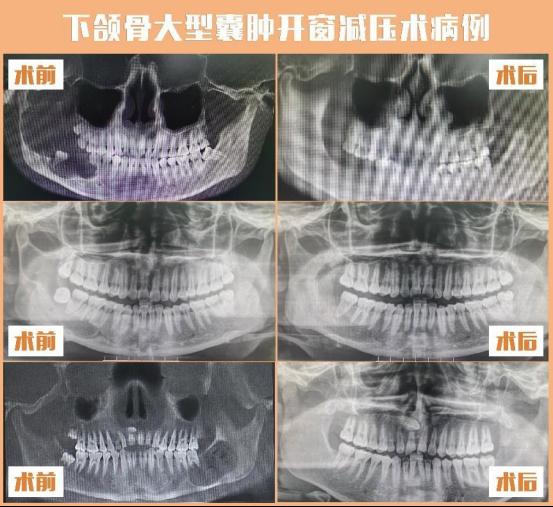

王冬香所在的颅颌面畸形正颌外科团队,是贵州省首家开展正颌外科手术的团队,2018年开展数字化外科设计方案,采用3D打印模型指导手术,使手术更精准,获得面部外形及功能俱佳的治疗效果,其学科水平处于国内领先。王冬香主持开展的院级新技术新项目3D打印塞治器在大型下颌骨囊肿中的应用,遵循功能外科及微创外科的理念,最大限度的保留颌骨外形,创伤小,并发症少,使患者获得更加简单、微创、舒适、经济、有效的治疗。

正颌外科手术病例